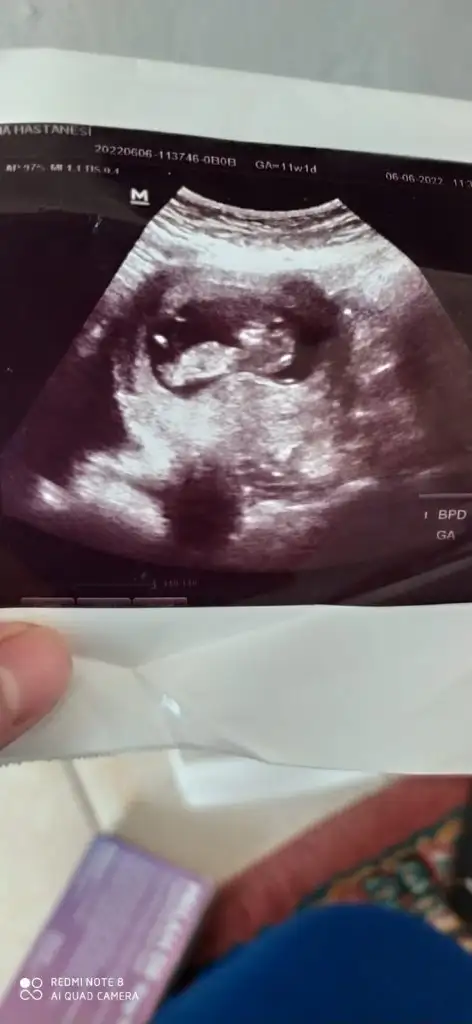

Merhaba 8 haftalık karından bakıldı

• IMG-20220628-WA0001.webp

IMG-20220628-WA0001.webp

14,9 KB · Görüntüleme: 74

Merhaba 7 buçuk haftalık tahmin ederseniz sevinirim☺️

• IMG-20220628-WA0005.webp

IMG-20220628-WA0005.webp

21,7 KB · Görüntüleme: 67

• IMG-20220628-WA0006.webp

IMG-20220628-WA0006.webp

18,8 KB · Görüntüleme: 74